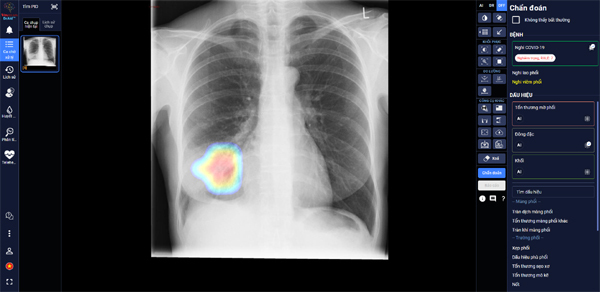

Sau hơn 1 năm nghiên cứu và phát triển, mới đây, VinBrain đã công bố hoàn thiện sản phẩm DrAid cho Covid-19 với khả năng giải toàn diện bài toán Covid-19 từ hỗ trợ chẩn đoán tới tiên lượng điều trị dựa trên ảnh X-quang ngực thẳng

| DrAid giúp bác sĩ theo dõi mức độ tổn thương phổi ở một bệnh nhân F0 trên ảnh X-quang phổi |

Trong các bệnh viện thu dung điều trị Covid-19, DrAid cho Covid-19 giúp các bác sĩ đánh giá mức độ tổn thương phổi của bệnh nhân Covid-19 qua các ngày, từ đó đưa ra các chỉ định điều trị kịp thời và hiệu quả cho bệnh nhân.